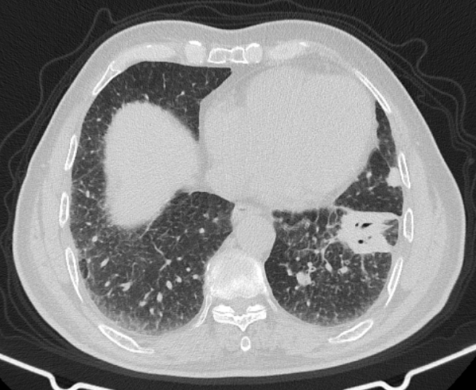

此次手术患者是喀什地区第一人民医院的一名55岁病人,因“间断咳嗽、咳痰、气短2年,再发5天”入院,术前CT显示“左下叶前内基底段囊实性病灶,边缘不规整,内部多发囊状影,约30*27mm”。(图1)

喀什地区第一人民医院的一名55岁病人术前CT(图1)